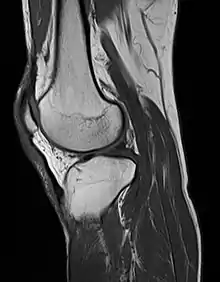

MRI uses strong magnetic fields to align atomic nuclei (usually hydrogen protons) within body tissues, then uses a radio signal to disturb the axis of rotation of these nuclei and observes the radio frequency signal generated as the nuclei return to their baseline states.[10] The radio signals are collected by small antennae, called coils, placed near the area of interest. An advantage of MRI is its ability to produce images in axial, coronal, sagittal and multiple oblique planes with equal ease. MRI scans give the best soft tissue contrast of all the imaging modalities. With advances in scanning speed and spatial resolution, and improvements in computer 3D algorithms and hardware, MRI has become an important tool in musculoskeletal radiology and neuroradiology.

One disadvantage is the patient has to hold still for long periods of time in a noisy, cramped space while the imaging is performed. Claustrophobia (fear of closed spaces) severe enough to terminate the MRI exam is reported in up to 5% of patients. Recent improvements in magnet design including stronger magnetic fields (3 teslas), shortening exam times, wider, shorter magnet bores and more open magnet designs, have brought some relief for claustrophobic patients. However, for magnets with equivalent field strengths, there is often a trade-off between image quality and open design. MRI has great benefit in imaging the brain, spine, and musculoskeletal system. The use of MRI is currently contraindicated for patients with pacemakers, cochlear implants, some indwelling medication pumps, certain types of cerebral aneurysm clips, metal fragments in the eyes and some metallic hardware due to the powerful magnetic fields and strong fluctuating radio signals to which the body is exposed. Areas of potential advancement include functional imaging, cardiovascular MRI, and MRI-guided therapy.